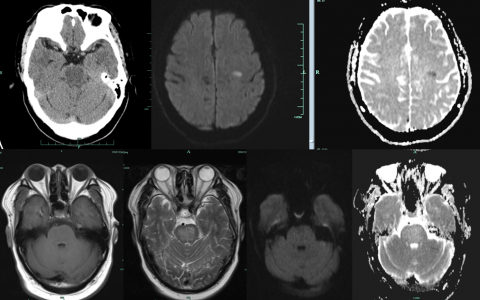

A 50-year-old man is brought to the emergency department encephalopathic, with a Glasgow C…